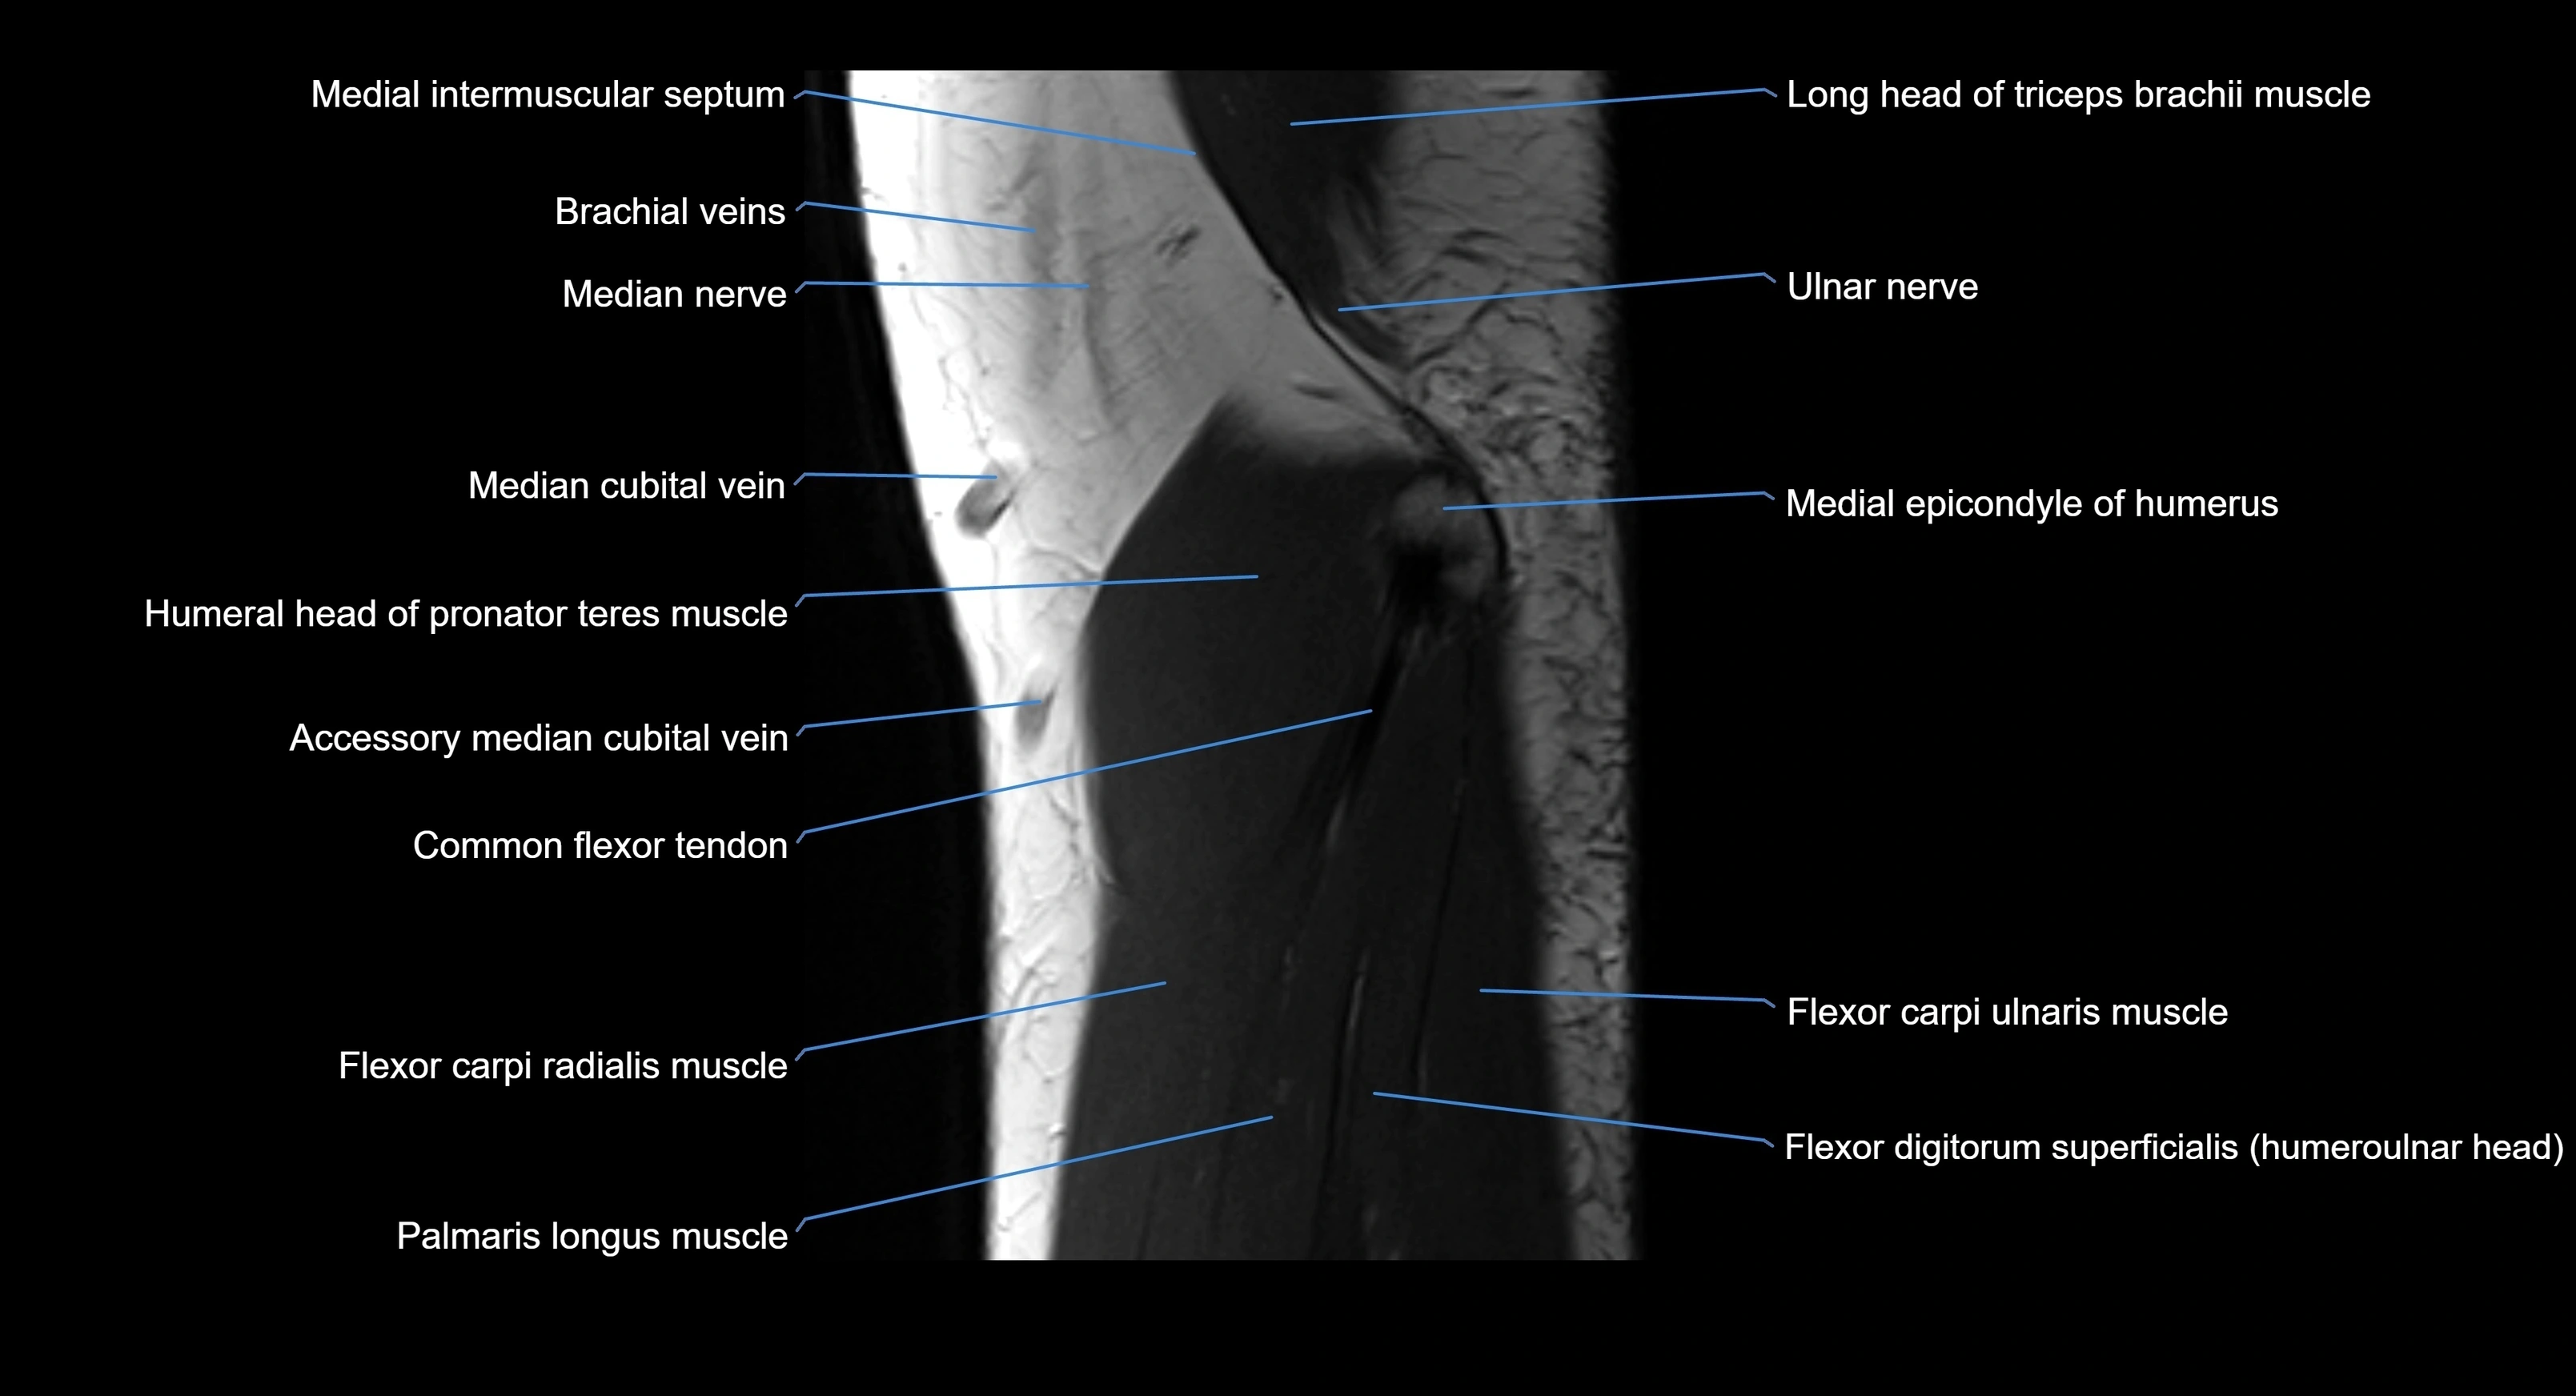

MRI image

image